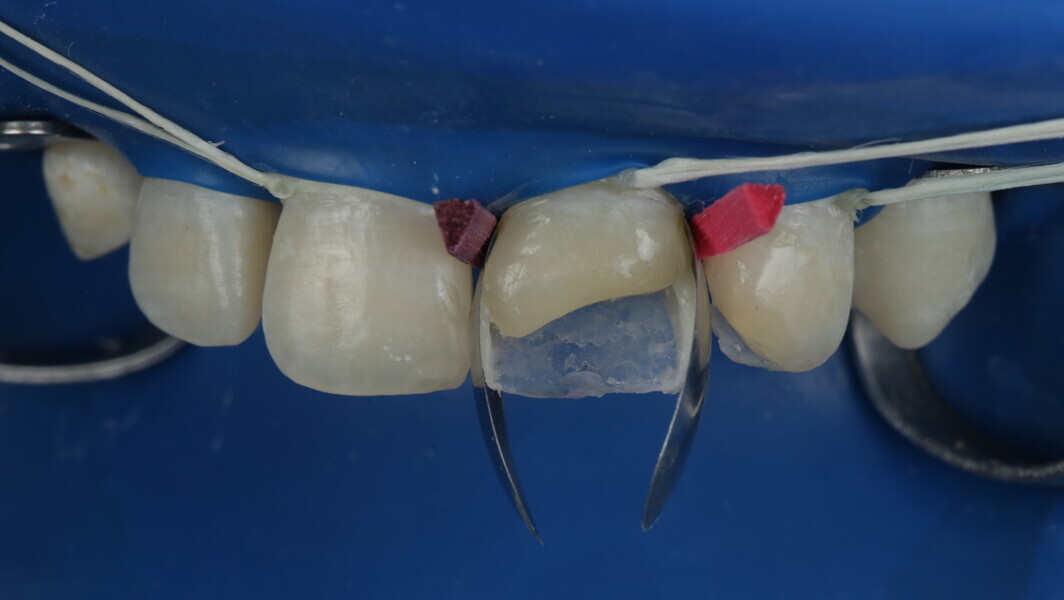

Fig 19-24: Contact build-up with band and wedge

Fig 25-30: Layering protocol step by step